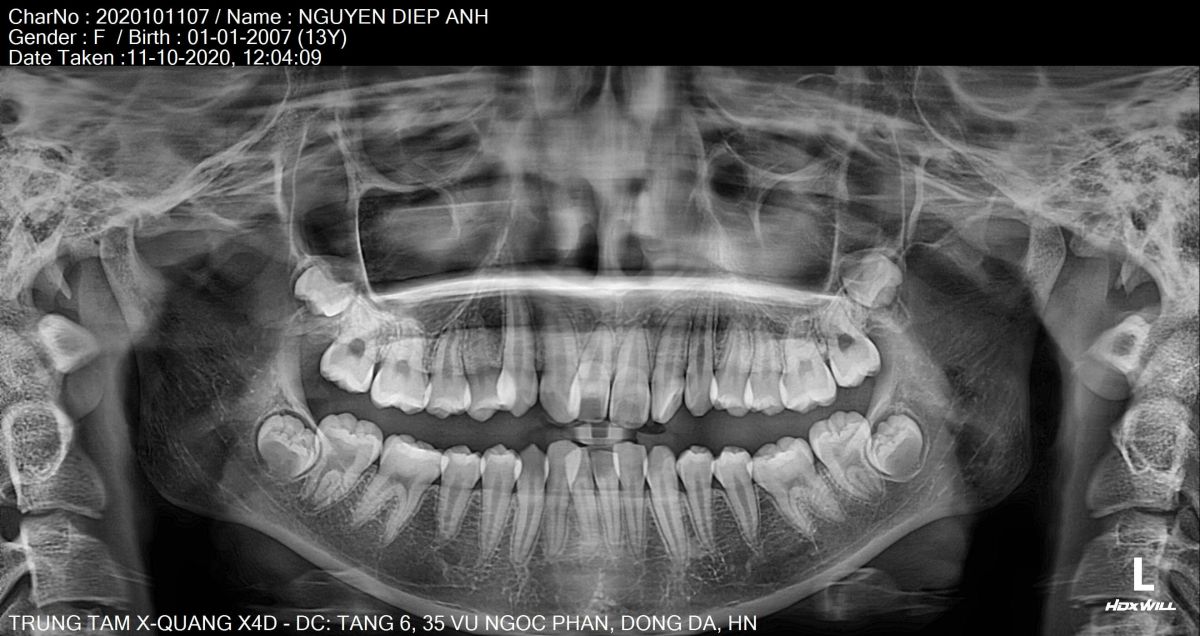

Sau khi thăm khám tại Nha khoa Hanseoul, bác sĩ ghi nhận các vấn đề:- Răng lệch lạc, chen chúc nghiêm trọng cả hai hàm

- Không đủ khoảng sắp xếp răng

- Khớp cắn sai (cắn chìa – cắn sâu)

Bác sĩ chỉnh nha chuyên sâu trực tiếp xây dựng phác đồ dựa trên phim X-quang, hình ảnh 3D và phân tích khớp cắn, đảm bảo răng di chuyển đúng hướng – đúng lực – đúng thời điểm.